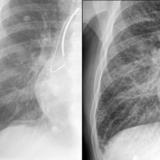

IPE before and after

Date: 02/07/2010

Views: 3120